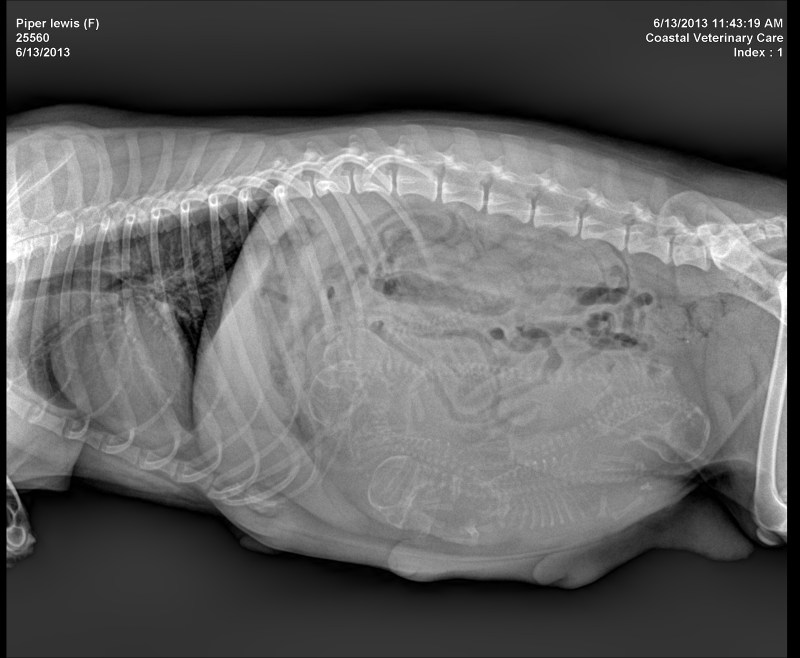

Pipers X-Ray

Pipers x-ray at day 60

shows 5 pups.